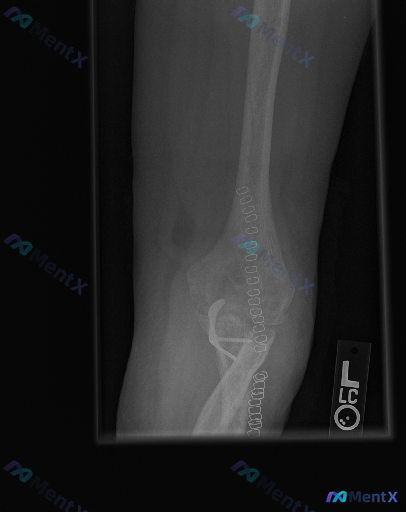

整理了一份肘关节术后的侧位X光影像分析资料,先不直接给结论,大家一起来看看读片思路。 影像基本情况 - 标记为左侧(L)肘关节侧位片 - 可见肱骨远端、尺骨近端的金属内固定系统(钢板、螺钉),还有串珠状高密度缝合钉影 - 术区有金属伪影干扰 - 局部可见骨密度增高区域(考虑骨痂形成迹象) - 目前未...

整理到一份影像读片资料,觉得很适合讨论临床思维里的“小陷阱”。 先不说结论,只看原始情境:有人拿到这张影像,第一定位错了,后面的分析全偏了。再仔细看,还有个更大的问题——金属伪影把关键区域挡住了,看似“没明显异常”,其实什么都没法确定。 大家觉得: 1. 拿到这类带内固定的复查片,第一步最应该先确认...